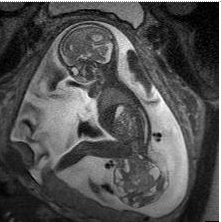

U quái vùng cùng cụt là khối u hay gặp nhất ở trẻ sơ sinh. Khối u này thường được da che phủ, nhưng cũng có thể được che phủ bởi một màng mô mỏng, trong suốt. Hầu hết các khối u có nhiều mạch máu nuôi dưỡng. Chúng có nhiều kích thước khác nhau, và đôi khi chúng có thể phát triển ra ngoài từ phía sau hoặc về phía bụng em bé.

SCT được phân loại dựa theo vị trí và mức độ nặng, cụ thể:

- Nhóm I: khối u ở bên ngoài cơ thể và bám vào phần xương đuôi.

- Nhóm II: khối u ở cả bên trong và ngoài cơ thể.

- Nhóm III: có thể được nhìn thấy từ bên ngoài, nhưng phần lớn khối u nằm bên trong ổ bụng em bé.

- Nhóm IV: là nhóm nguy hiểm nhất, không thể thấy được từ bên ngoài. Chúng nằm trong cơ thể ngang vị trí xương đuôi.

Theo đó, bụng mẹ lớn bất thường là dấu hiệu hay gặp đầu tiên gợi ý thai nhi có khối u. Kích thước tử cung lớn hơn bình thường có thể do khối u lớn hoặc do đa ối. Các biểu hiện ít gặp hơn bao gồm tiền sản giật ở mẹ. U vùng cùng cụt thai nhi có thể ở dạng nang, dạng đặc hoặc dạng hỗn hợp trên hình ảnh siêu âm. Hình ảnh mật độ không đồng nhất của khối u có thể do vùng hỗn hợp của khối u hoại tử, thoái hóa nang, xuất huyết hoặc canxi hóa.